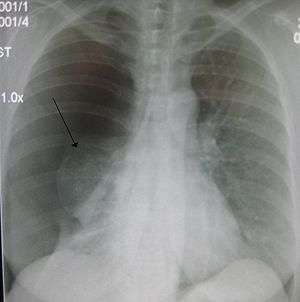

A large right-sided spontaneous pneumothorax (left in the image). An arrow indicates the edge of the collapsed lung

Chest X-ray

Chest X-ray of left-sided pneumothorax (seen on the right in this image). The left thoracic cavity is partly filled with air occupying the pleural space. The mediastinum is shifted to the opposite side.

Chest X-ray showing the features of pneumothorax

Traditionally a plain radiograph of the chest, ideally with the X-ray beams being projected from the back (posteroanterior, or "PA"), has been the most appropriate first investigation. These are usually performed during maximal inspiration (holding one's breath); no added information is gathered by obtaining a chest X-ray in expiration (after exhaling).[12][13] If the PA X-ray does not show a pneumothorax but there is a strong suspicion of one, lateral X-rays (with beams projecting from the side) may be performed, but this is not routine practice.[13][17] It is not unusual for the mediastinum (the structure between the lungs that contains the heart, great blood vessels and large airways) to be shifted away from the affected lung due to the pressure differences. This is not equivalent to a tension pneumothorax, which is determined mainly by the constellation of symptoms, hypoxia, and shock.[12]

The size of the pneumothorax (i.e. the volume of air in the pleural space) can be determined with a reasonable degree of accuracy by measuring the distance between the chest wall and the lung. This is relevant to treatment, as smaller pneumothoraces may be managed differently. An air rim of 2 cm means that the pneumothorax occupies about 50% of the hemithorax.[13] British professional guidelines have traditionally stated that the measurement should be performed at the level of the hilum (where blood vessels and airways enter the lung) with 2 cm as the cutoff,[13] while American guidelines state that the measurement should be done at the apex (top) of the lung with 3 cm differentiating between a "small" and a "large" pneumothorax.[23] The latter method may overestimate the size of a pneumothorax if it is located mainly at the apex, which is a common occurrence.[13] The various methods correlate poorly, but are the best easily available ways of estimating pneumothorax size.[13][17] CT scanning (see below) can provide a more accurate determination of the size of the pneumothorax, but its routine use in this setting is not recommended.[23]